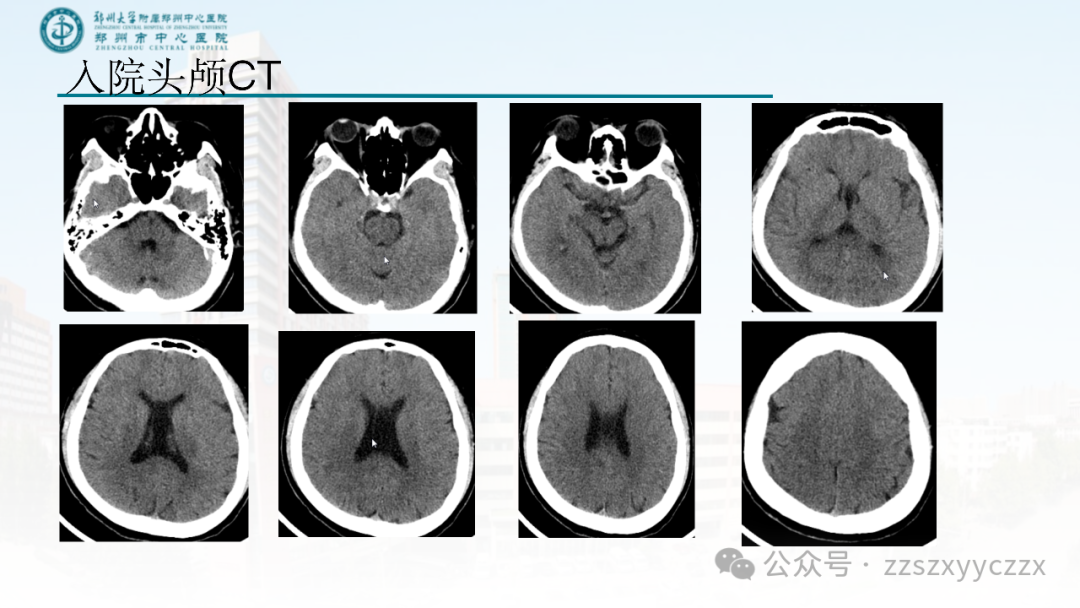

脑卒中病例分析—PFO与脑梗死

本文对一个急性缺血性脑卒中患者的病因进行了抽丝剥茧的分析,找出了这例患者的病因:PFO(卵圆孔未闭),同时进行了相关文献的复习。